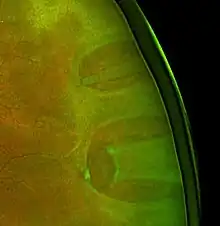

![]() | |

| Ultrasound of a retinal detachment in a patient presenting with complete vision loss and light perception only. | |